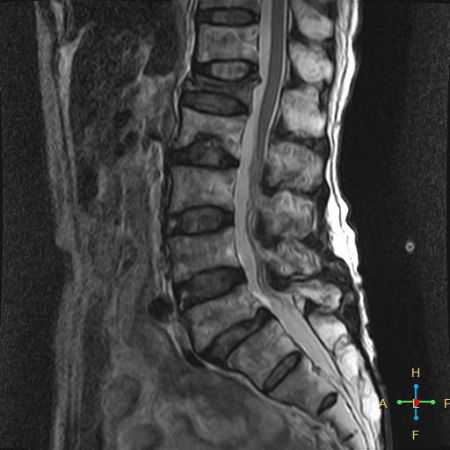

2 良性压缩性骨折 椎体形态:楔形、凹陷形。 椎体连续性病变(骨质疏松):新鲜、陈旧骨折并存。

椎间盘改变:椎间盘增厚呈双凸透镜状, 椎间盘疝入椎体, 形成许莫氏结节。

椎体后上角或后下角向后翘起, 呈尖突样突入椎管, 具有特异性,为其它原因的骨折所少见。

4 总结:鉴别诊断 ——良性压缩性骨折—— 楔形或凹陷形 连续性分布 椎间盘增厚双凸状,许莫氏结节 急性期T1WI不均匀低信号 椎体后角翘起突入椎管内 椎体后角回避现象 可伴椎弓根水肿、无膨大 椎旁薄环形软组织影